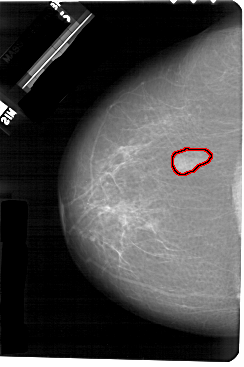

FILE: A_1266_1.LEFT_MLO.OVERLAY

TOTAL_ABNORMALITIES 1

ABNORMALITY 1

LESION_TYPE MASS SHAPE LOBULATED MARGINS ILL_DEFINED

ASSESSMENT 3

SUBTLETY 5

PATHOLOGY BENIGN

TOTAL_OUTLINES 1

BOUNDARY

LEFT_MLO LINES 5491 PIXELS_PER_LINE 3586 BITS_PER_PIXEL 12 RESOLUTION 43.5 OVERLAY